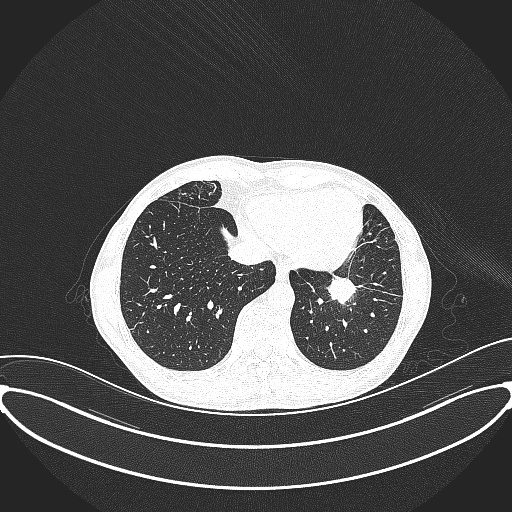

心胸外科实施的微波消融术是在CT引导下,将一根直径仅2mm的微波针穿刺到肿瘤部位,使肿瘤局部温度瞬间升高到80-100℃,实现“烧死”肿瘤的目标。该术式创伤小、安全性高、疗效好,可以提高患者的生活质量,并延长生存时间,是目前应用前景较好的治疗方式之一。术后4至6周复查胸部增强CT,并以此为基线进行评价,术后2年内每3个月复查胸部CT,2年后每6个月复查一次。

术前与术中对比图